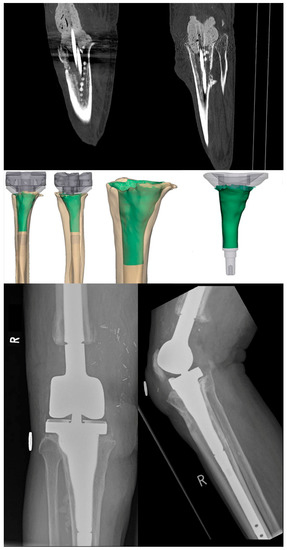

2. Therapy Algorithm and Implant Design

4. Results

5. Design Adaptations